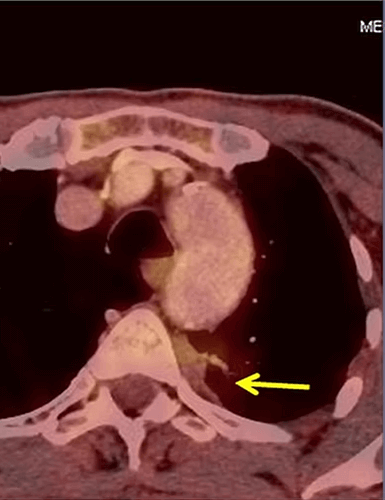

In our patient with lung cancer, PET-CT shows the large tumor (arrow). After 3 sessions of intraarterial chemotherapy, the control PET-CT showed almost complete disappearance of the tumor.